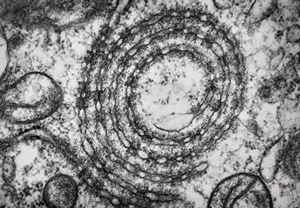

M,26y. | ribosome-lamella bodies in adenocarcinoma

M,41y. | ribosome-lamella complex in tricholeukocyte -hairy cell leukemia, spleen

M,41y. | ribosome-lamella complex in tricholeukocyte -hairy cell leukemia, spleen

M,41y. | ribosome-lamella complex in tricholeukocyte -hairy cell leukemia, spleen